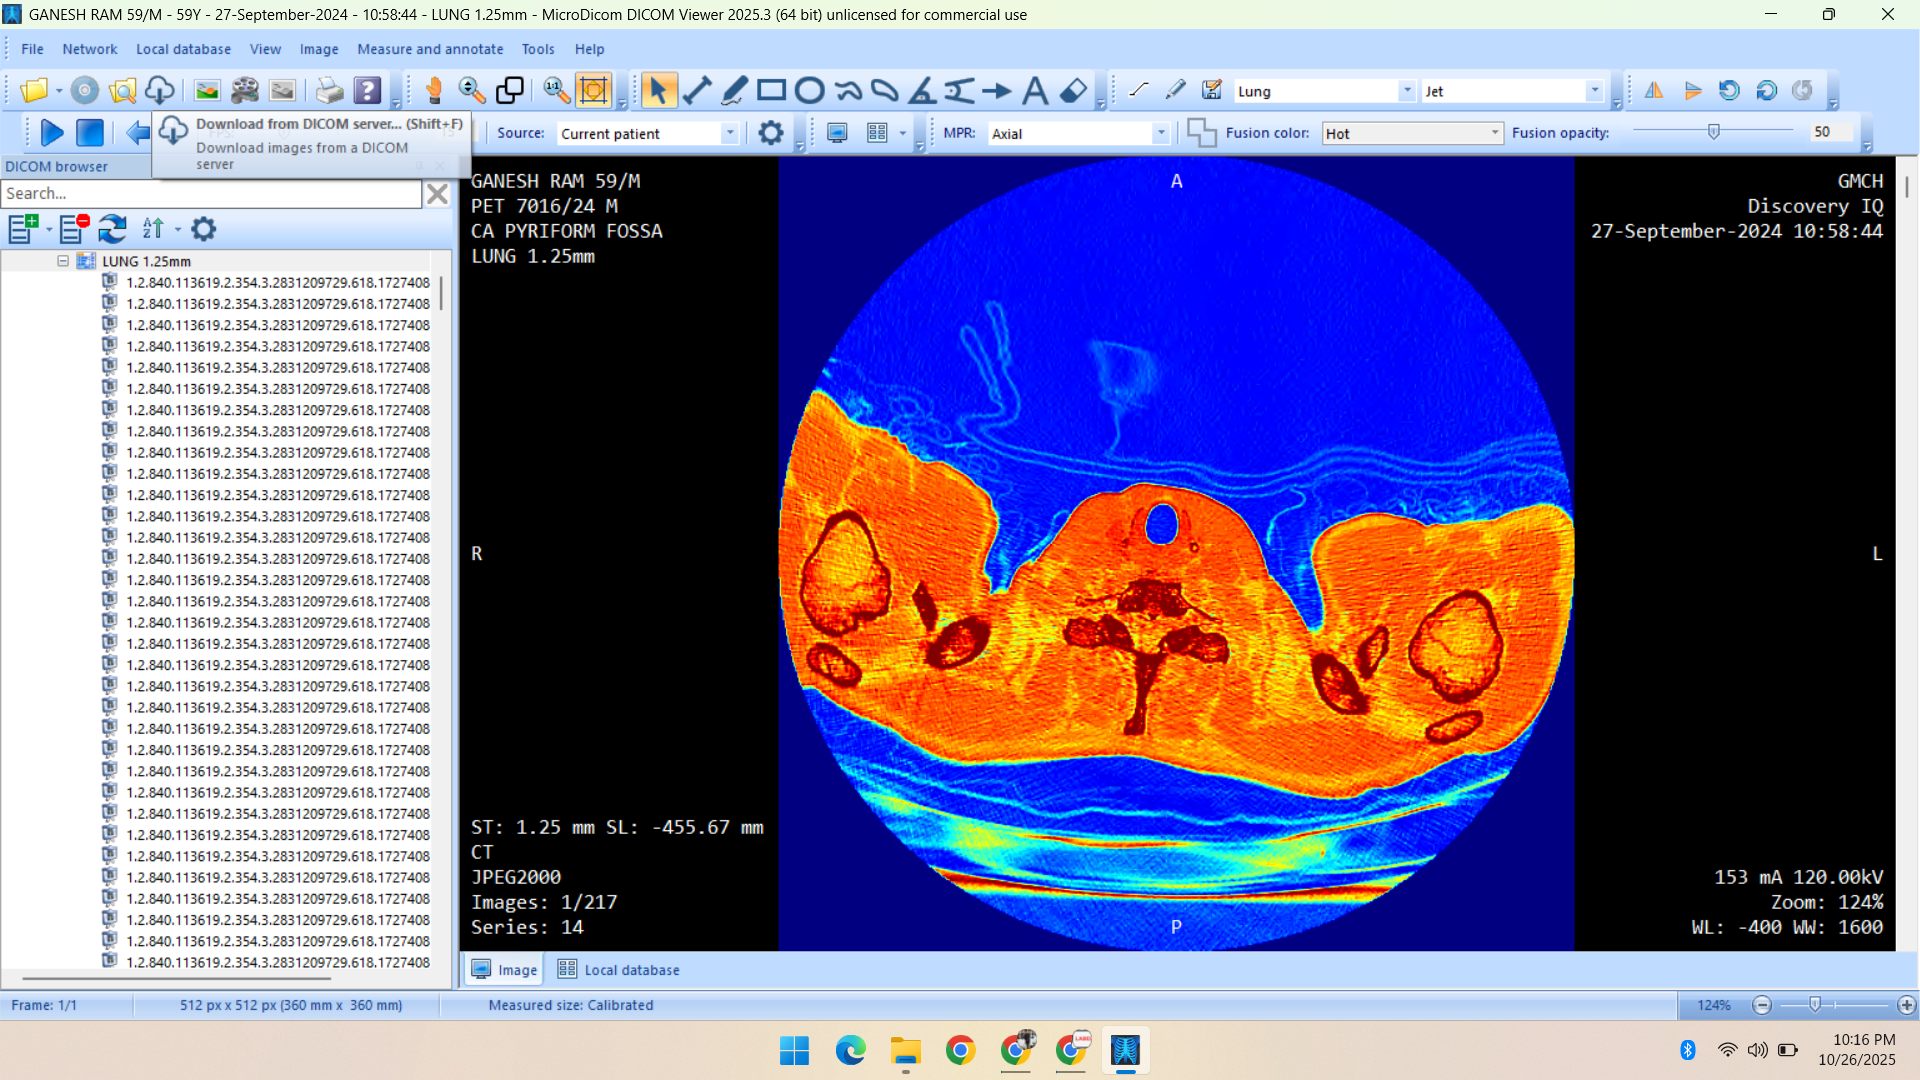

- Radiology Data – CT Scans, X-Rays, MRI, Echocardiography, Ultrasound.

Healthcare & Medical Data Supply

We specialize in healthcare datasets including radiology (CT, X-ray, MRI, Ultrasound, Echocardiography), pathology microscopy, and histopathology images — all ethically sourced and research-ready.

Portfolio

Showcasing Innovative AI Solutions and Data Services: Delivering Quality Data for Smarter, Future-Ready Applications

- CT Scan

- PET Scan